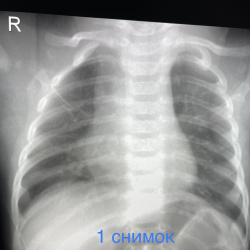

Добрый день. Подскажите пожалуйтса как описать в нижних отделах левого легкого.. как образование слева ?